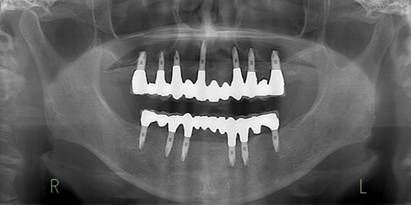

術前パノラマレントゲン写真。根の周りが黒くなり、骨がなくなっていることがわかります

治療後。歯周病で失われた骨が回復しています。使用インプラントはスプラインツイストです。